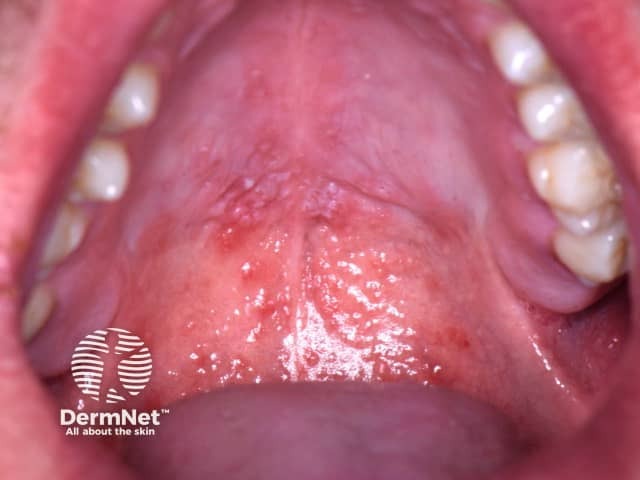

6.11 Oral candidiasis

Oral candidiasis (thrush) is an overgrowth of oral candida albicans. Candida albicans is a yeast-like fungus that is present in many foods and is part of the healthy bacterial flora that live in the mouths of around half the Australian population.

Image sourced from DermNet

Prevalence

Relatively common; often seen in babies or infants, or individuals on long term antibiotics or immuno-suppressive drugs

Signs and symptoms

The yeast affects the superficial layers of the mouth tissues. Thrush is generally a local surface infection that produces milky white patches in the mouth that can not be easily wiped off the oral mucosa. Oral infection may be associated with infection in the nappy area. Very rarely, fever and gastrointestinal irritation may accompany the disorder, and this signifies a more general infection.

Causes

Overgrowth of candida albicans. Candidiasis can be caused by inhaled cortico-steroids used to treat asthma. Parents should rinse children’s mouth with water after inhalation to reduce the likelihood of infection.

Age

Candidiasis commonly occurs in young babies and infants.

Duration

Infection can persist for days or weeks.

Treatment

Referral to a dental practitioner is required. Treatment consists of topical anti fungal agents applied directly to the affected areas